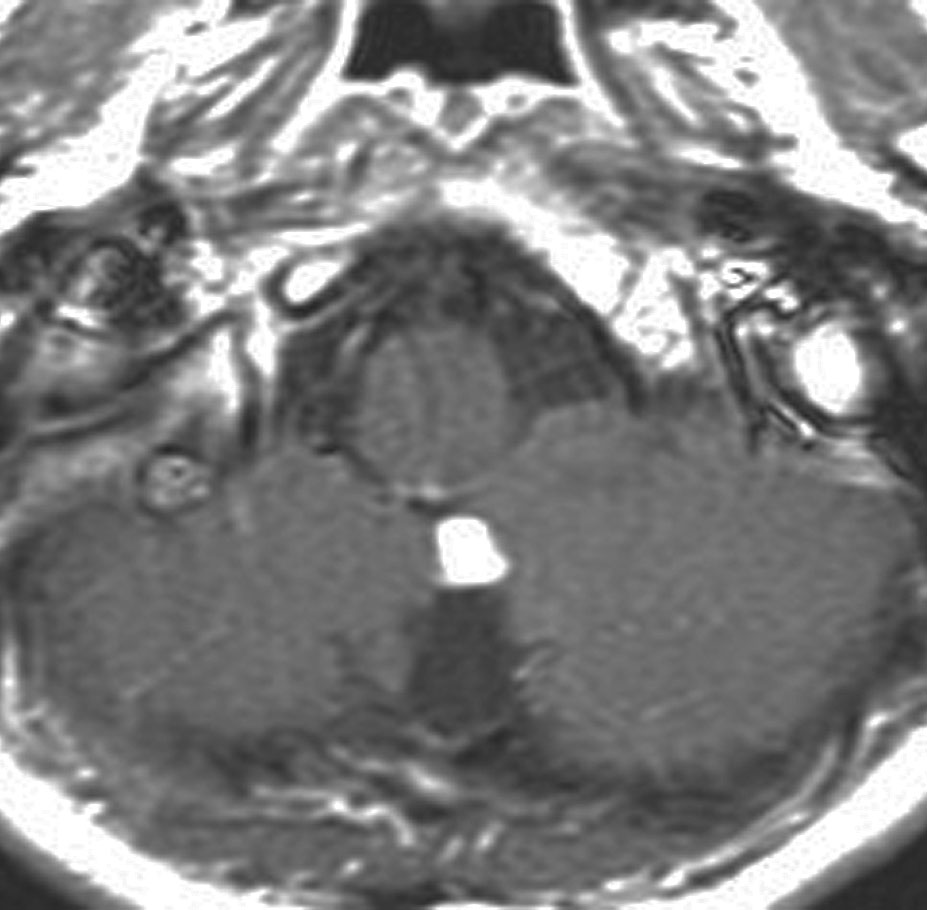

小脳毛様細胞性星細胞腫のFLAIR画像所見

壁在結節を伴うのう胞性小脳毛様細胞性星細胞腫は,結節を手術摘出すれば治癒するものです。しかし,あたかも腫瘍が残っているようなMRI画像所見が残ることがあります。

この例は,10歳の子どもに無症状で偶然発見された大きなのう胞性小脳毛様細胞性星細胞腫です。開頭手術で腫瘍結節は全摘出して腫瘍のう胞は縮小したままです。(画像はクリックすると拡大して見えます)

開頭手術で白く増強される結節部分だけを摘出しました。MIB-1はやや高値で3%と報告されました。病理組織診断は,WHO grade 1 毛様細胞性星細胞腫です。

6年後のMRI FLAIR画像です。摘出腔周囲の高信号域が残存しています。ここまで残ると腫瘍周辺浮腫ではありませんし,腫瘍細胞が左小脳半球に広範囲に浸潤して残存しているものだと判断されます。しかし,6年間で病変の増大傾向がありませんでした。この残存腫瘍(らしい所見)に対して放射線治療や化学療法を行うべきかどうか,結論は出ていません。しかし,経過観察を続けても増大して来ない例があることは確かです。一方で,この高信号領域が拡大したり,ガドリニウム増強される病変が再出現して治療がまた必用となることもあります。